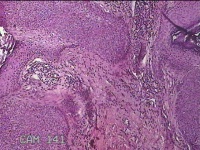

右侧肩部红色结节

性别

女

年龄

48岁

临床诊断

皮下结节

一般病史

发现右侧肩部结节3年余。

标本名称

大体所见

灰白暗红色结节0.5x0.3x0.2cm一个,表面糜烂。

基底细胞乳头状瘤